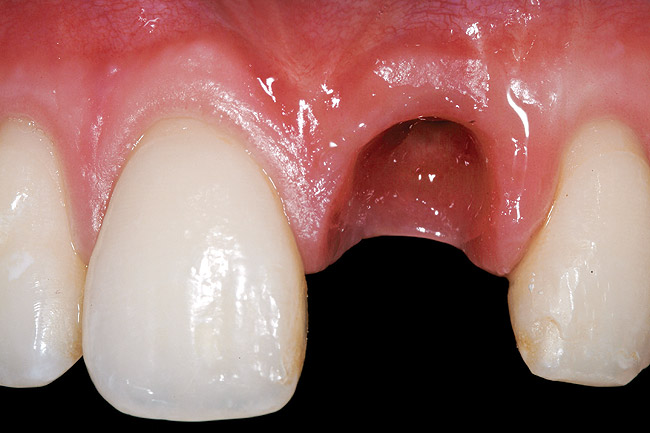

A 27-year-old non-smoking man presented for esthetic enhancement of the left central incisor, which had a pre-existing full-coverage restoration that required replacement (Figure 16). The patient had begun orthodontic treatment in the mandibular arch to correct a minor occlusal imbalance and required coronal repositioning and soft tissue grafting to correct gingival recession at the facial of the right canine, in addition to correction of the free gingival margin at the facial of the left central incisor, which was asymmetrical to the free gingival margin of tooth No. 8. Additionally, the facial gingival tissues were of a thin biotype, which at the facial surface of the left central incisor allowed for the darkened root surface to be visible through the tissue (Figure 16).

Figure 16  Case Two Preoperative clinical view, maxillary left central incisor.

Figure 16